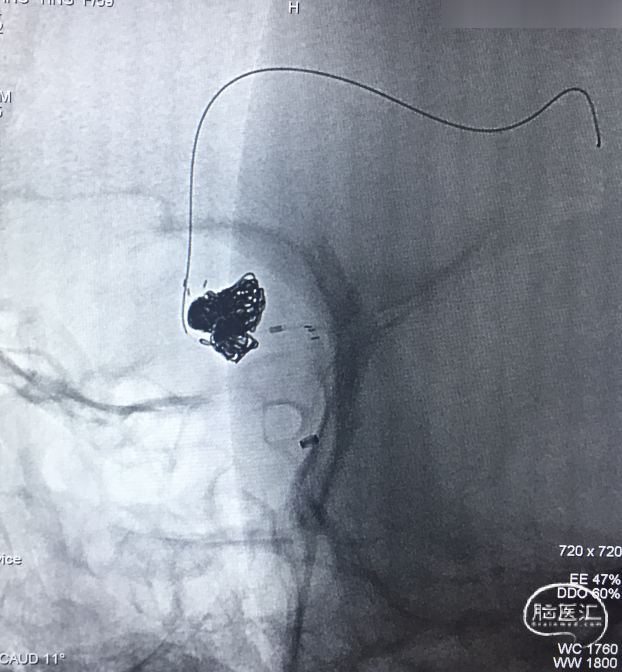

栓塞过程

直头SL-10及S头SL-10先后交互填圈,分区致密栓塞动脉瘤。

支架内球囊扩张

Synchro(200cm)携Echelon-10到达RACA A3(左图)。Synchro(300cm)交换Gateway1.5×9mm及Ultra-soft SV 2.0×20mm支架内扩张(6 atm)(右图)。